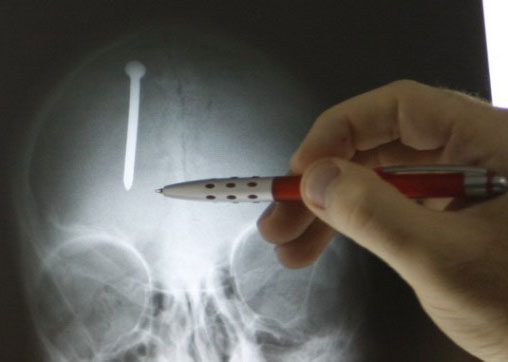

Un sibian in varstă de 38 de ani s-a automutilat după o beţie cu amicii. Supărat pe prietenii cu care a băut, bărbatul, fost puşcăriaş şi-a bătut cu piatra cuiul în cap, dorind astfel să le demonstreze acestora ce a învăţat între zidurile puşcăriei.

Acesta fost dus la spitalul de urgenţa din Timiş unde a fost supus unei intervenţie chirurgicală. Medicii susţin că dacă i-ar fi intrat în cap încă o jumătate de centimetru din cui acesta ar fi murit. Momentan starea sa este stabilă, însă există riscul apariţiei unei infecţii. Sibianul va rămâne sub supraveghere medicală cel puţin o săptămână, iar la externare medicii îi vor recomanda un psihiatru.